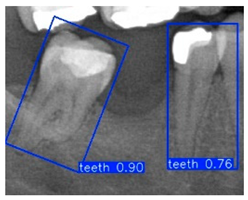

| YOLO-OBB result | ||||||

| Validation Image 1–6 | ![]() | ![]() | ![]() | ![]() | ![]() | ![]() |

| Accuracy | 84.13% 75.18% | 90.29% 76.49% | 87.38% 87.27% | 80.40% 84.48% | 70.11% 83.41% | 88.46% 76.33% |